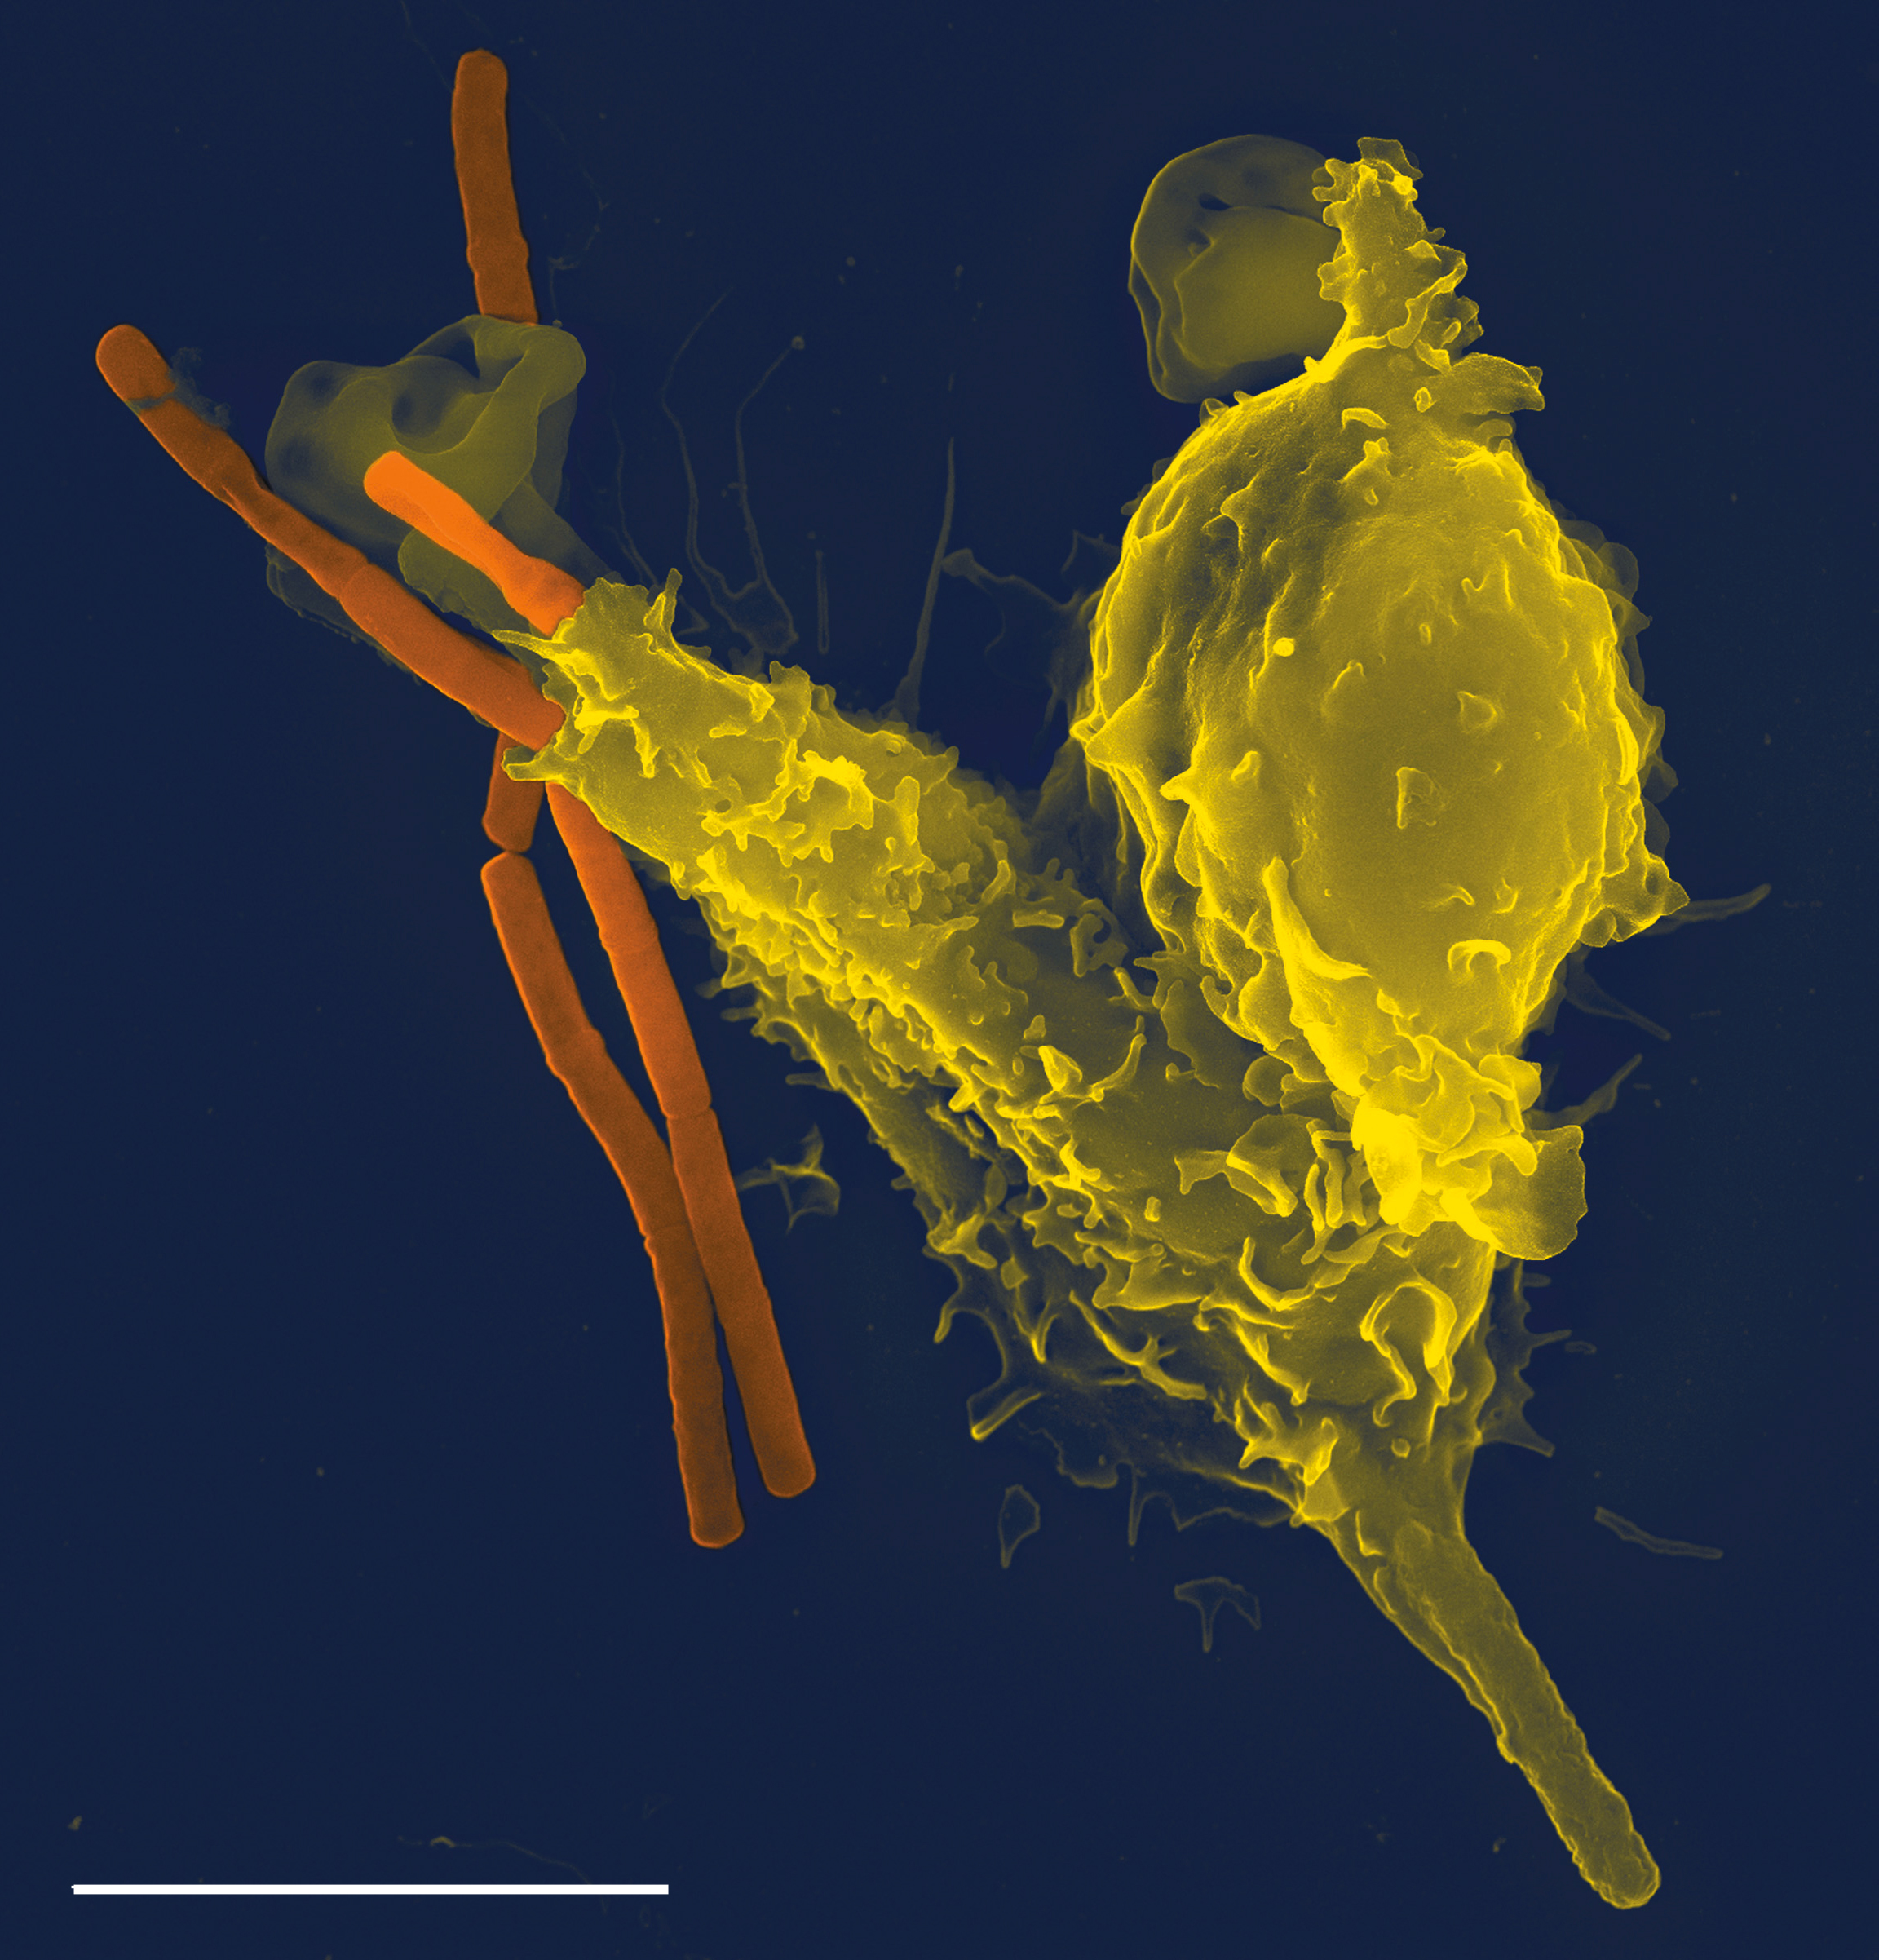

This kind of pulmonary nodule forms as a side-effect of your body's inflammatory response. This response gets triggered whenever your body detects irritation or infection in your lungs, and it helps your immune system fight off the invader.

As part of the inflammatory response, a granuloma, or a small patch of inflamed tissue, can form at the site of irritation or infection. Granulomas are your immune system's way of isolating the infection and preventing it from spreading to surrounding areas.

However, over time calcium deposits can form in the granuloma, leaving behind a permanent spot of calcified tissue. That spot is now a pulmonary nodule that can show up on chest scans long after the original source of irritation is gone.

This type of of pulmonary nodule is usually harmless, asymptomatic, and doesn't grow or change. It is like a scar; just a patch of tissue that's healed over but looks slightly different than it did before.